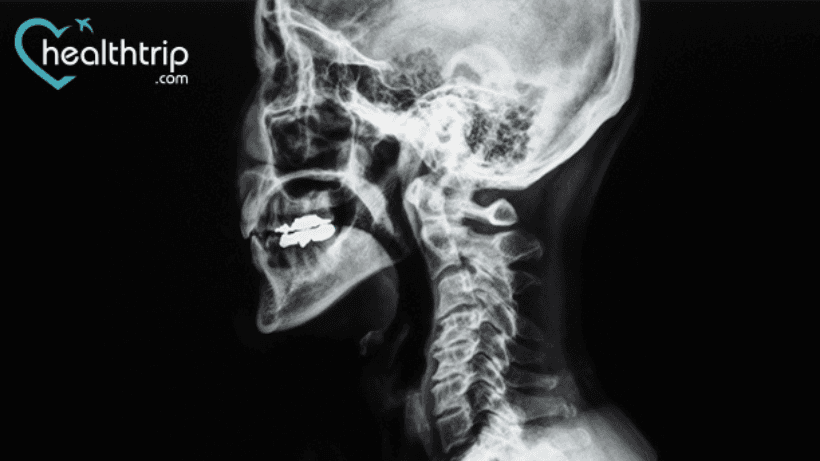

የተጎዱ ዲስኮችን ወይም የአጥንት መነሳሳትን ለማስወገድ የፊተኛው የማህጸን ጫፍ ዲስኬቶሚ እና ፊውዥን (ACDF) ቀዶ ጥገና በአንገትዎ ላይ ይደረጋል።. እና እንደዚህ አይነት ቀዶ ጥገናዎች ምን ያህል አመታት እንደሚቆዩ ለማወቅ ከፈለጉ, በትክክለኛው ገጽ ላይ ነዎት.. እዚህ ላይ የስኬት መጠኑን እና ሌሎች ከእንደዚህ አይነት ህክምና በኋላ ማወቅ ያለብዎትን እውነታዎች በአጭሩ ተወያይተናል የሕክምና ሕክምና.

ACDF ለሁሉም የመጀመሪያ ደረጃ ምርመራዎች ውጤቶችን ያሻሽላል እና ከአስር አመታት በላይ እንደሚቆይ ታይቷል. ሁለተኛ ደረጃ ቀዶ ጥገናዎች የተከናወኑት pseudarthrosis ለመጠገን እና ምልክቶችን በአቅራቢያው ያለውን ደረጃ መበላሸትን ለማከም ነው..

ይህ ቀዶ ጥገና በጣም የተሳካ ነው. በክንድ ህመም ምክንያት ACDF ቀዶ ጥገና ያደረጉ ሰዎች ከ93 እስከ 100 በመቶ ከሚሆኑት ጉዳዮች ላይ የህመም ማስታገሻ ያደረጉ ሲሆን ለአንገት ህመም ACDF ቀዶ ጥገና ያደረጉ ሰዎች ከ73 እስከ 83 በመቶ ከሚሆኑት ጉዳዮች ላይ አወንታዊ ውጤቶችን ዘግበዋል።.